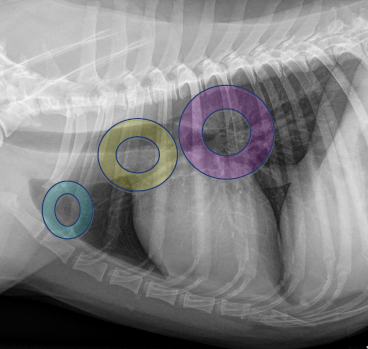

Sternal lymph node

Mediastinal lymph node

Tracheobronchial lymph node

Thymus